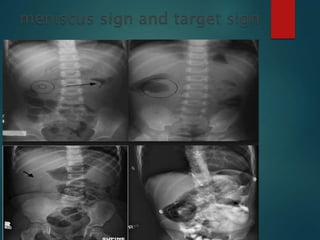

The rounded barium column

suddenly becomes concave

Forms a meniscus around the head of

the intussusception

When the intussusception is displaced,

the meniscus flattens out

Barium seeps between the two and produces

the characteristic radiologic appearance of a

coiled spring

The rounded bariumcolumn suddenly becomes concave Forms a meniscus around the head of the intussusception When the intussusception is displaced, the meniscus flattens out

• 58.

Barium seeps betweenthe two and produces the characteristic radiologic appearance of a coiled spring Filling of the cecum is often slow, the sudden rush of barium into the distal ileum indicative of reduction